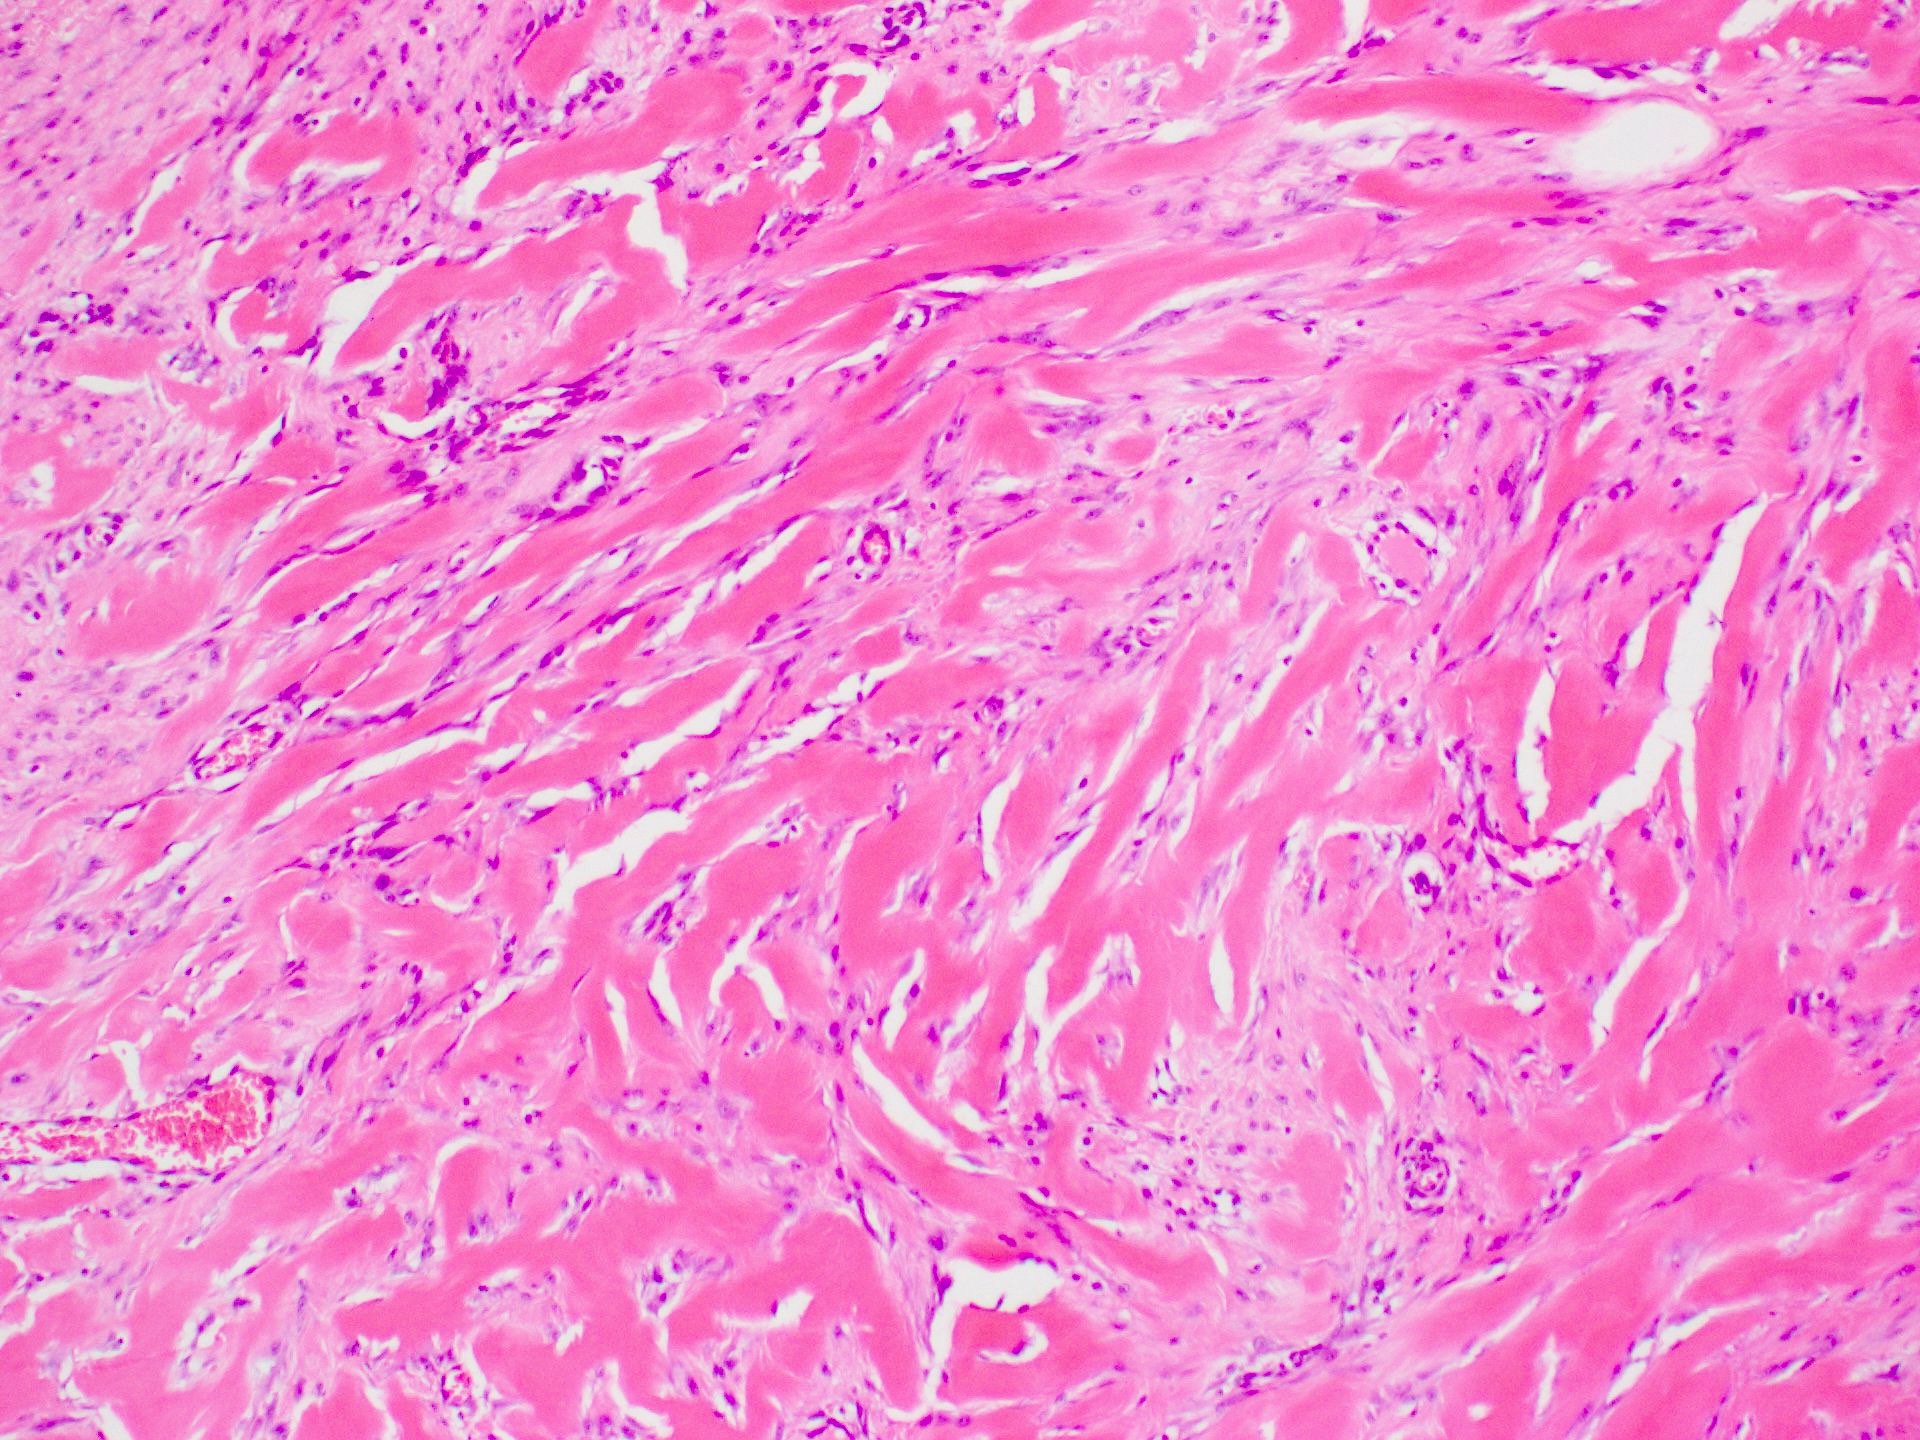

Microscopic (histologic) description

- Characteristic long, broad, closely packed collagen bundles that stain uniformly eosinophilic (keloidal collagen) arranged in haphazard fascicles (Scars Burn Heal 2021;7:2059513120980320)

- Fibroblasts are increased compared to normal skin (Front Cell Dev Biol 2020;8:360)

- May appear edematous due to increased dermal mucosubstances (J Zhejiang Univ Sci B 2022;23:699)

- Fewer capillaries and blood vessels than surrounding skin (J Plast Surg Hand Surg 2010;44:272)

- Tend to have marked inflammation in the dermis at the leading edge of growing keloids (Scars Burn Heal 2021;7:2059513120980320)

Microscopic (histologic) images

C. Keloid. The image shows the classic and characteristic appearance of keloidal collagen. Answer A is incorrect because while dermatofibroma can be similar in appearance, it is typically more cellular and is most common on the legs. Answer B is incorrect because while hypertrophic scars can overlap in histological appearance with keloid, they are generally more cellular and have less keloidal collagen. Clinical history helps to make the diagnosis as Asian individuals have a much higher risk, keloids are most common in young people (10 - 30 years old) and the earlobe is a typical site. Answer D is incorrect because while scleroderma / morphea can mimic keloid on a small biopsy, the collagen pattern is different (being more ordered and almost acellular) and the clinical history is not suggestive.